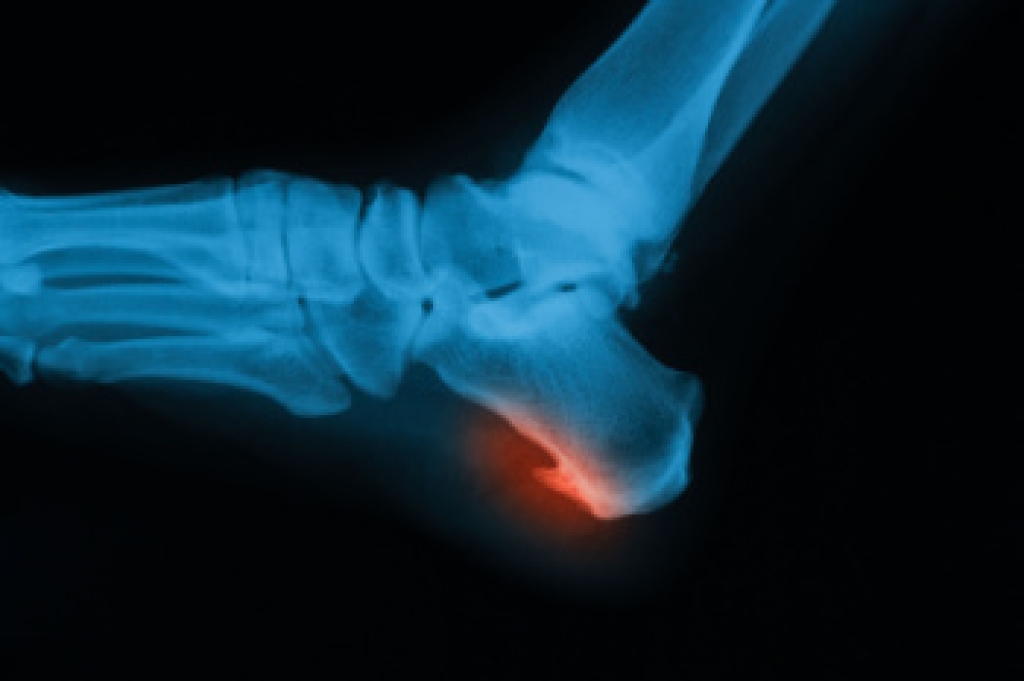

Heel spurs are bony growths that develop on the underside of the heel bone, often forming in response to long-term strain on foot muscles and ligaments. They can be caused by weakened muscles that fail to properly support the foot, joint stiffness that alters walking patterns, and repeated forced impact from walking or standing on hard floors. These factors place extra stress on the heel, leading to inflammation and pain. A podiatrist can diagnose heel spurs through examination and imaging, then recommend treatments like custom orthotics, stretching exercises, and supportive footwear. If heel pain is affecting your daily life, it is suggested that you consult a podiatrist who can accurately diagnose and treat heel spurs.

Heel spurs are formed by calcium deposits on the back of the foot where the heel is. This can also be caused by small fragments of bone breaking off one section of the foot, attaching onto the back of the foot. Heel spurs can also be bone growth on the back of the foot and may grow in the direction of the arch of the foot.

Older individuals usually suffer from heel spurs and pain sometimes intensifies with age. One of the main condition's spurs are related to is plantar fasciitis.